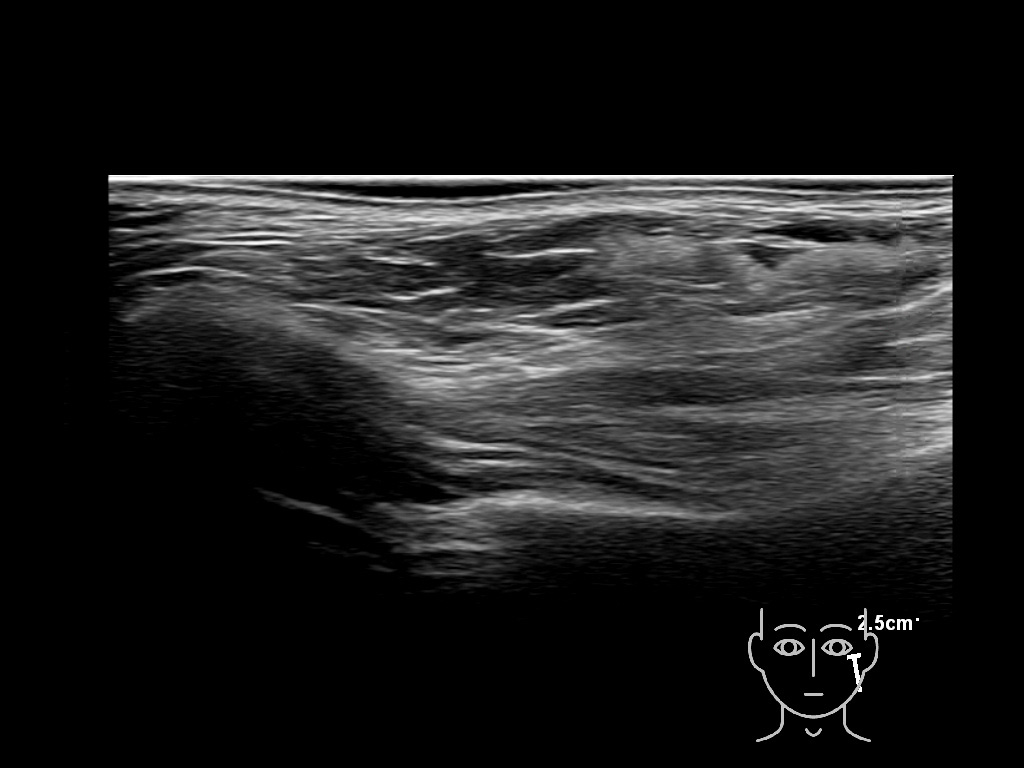

Draw in the image on the right where the fillers are located. To check if your answer is correct, please click on the secondary image.

Fillers

Draw in the second image below where the fillers are located. To check if your answer is correct, swipe the first image to the right.